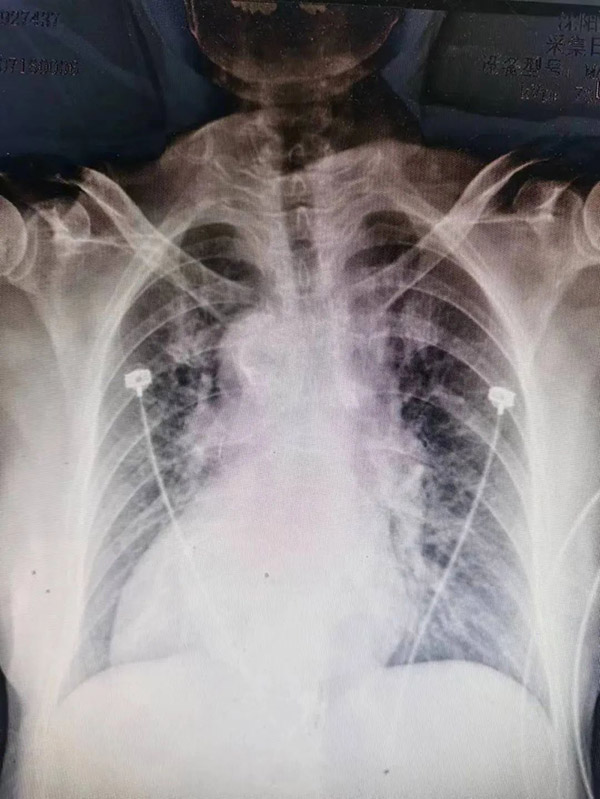

右位心 2023年7月15日15时23分市十院急诊科,78岁的李大姨胸痛剧烈,病情危重,心电图提示胸前导联ST段弓背向上抬高0.1-0.3mv,心肌损伤标志物数以万计。心脏中心佟铁壁主任第一时间赶到急诊,初步诊断急性前壁心肌梗死。检查时发现异样,心电图导联疑似左右手接反,而且左侧胸壁听不到心音,佟主任经过详细询问病史,查体及阅图,明确诊断患者为镜面右位心,右位心在临床上本就少见,合并急性心肌梗死的情况更是非常凶险,给医生心理及技术层面带来巨大的挑战!

由于患者特殊的生理结构,左冠状动脉位于心脏右侧,右冠状动脉位于心脏左侧,冠状动脉造影时,X线投照体位选择,导管送入冠脉开口的旋转动作应与一般患者的常规操作相反。加之,右位心易合并其他心脏畸形,或发生血管变异和走行异常 ,因此,右位心的介入治疗有着极大的风险及难度。但患者病情危重,意外随时可能发生,时间不等人,只能选择与死神博弈。

15时34分,患者被推入导管室,虽然已经做了术前评估和心理准备,但一到实操,大家还是如履薄冰。在佟主任带领下,团队充分发挥协作精神,改变惯有思维,谨慎操作。冠脉造影示:主要血管LAD开口90%狭窄,狭窄后100%闭塞,佟主任经慎重考量,经冠脉内溶栓及血栓抽吸,最后在LAD中远端置入支架一枚,血管顺利开通,TIMI血流3级,患者转危为安,大家如释重负。 术后患者被转入CCU病房,李海宁主任带领重症医学团队给予密切观察及术后精准治疗,使患者平稳度过危险期!3天后,患者安返普通病房,“太感谢你们了,是你们把我妈从鬼门关拉回来了啊”,每当管床医生李宏泽、护士长杨天舒查房时,李阿姨的孩子就兴奋对医生护士表示感谢。